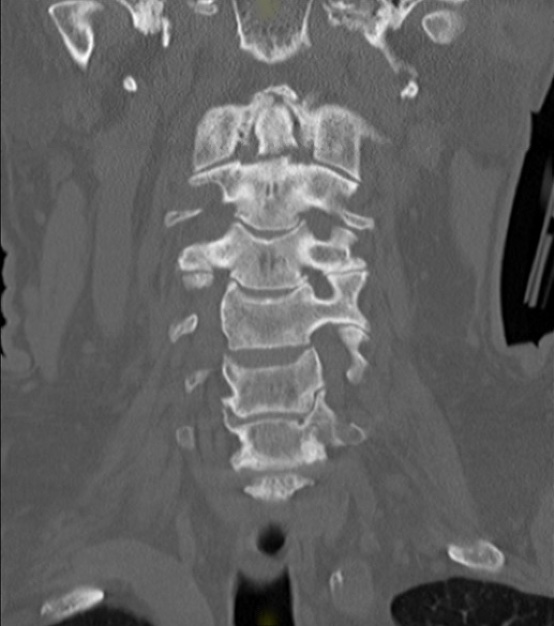

A70 yo male presents after MVC. He remembers waking up at the hospital with cervical collar in place and c/o neck pain. Denies numbness, tingling, weakness in extremities. He has midline cervical tenderness. He has full and symmetric strength in all four extremites as well as no sensory deficits. A CT cervical spine is shown (coronal). What's the diatnosis? Scroll down for answer.

Answer: Type II odontoid fracture

- Type I through the upper part of the odontoid peg (stable), Type II at the base of the odontoid peg (unstable), Type III through the odontoid and the lateral masses (unstable)

Type II odontoid fractures

- the most unstable of the three types

- occurs at base of odontoid